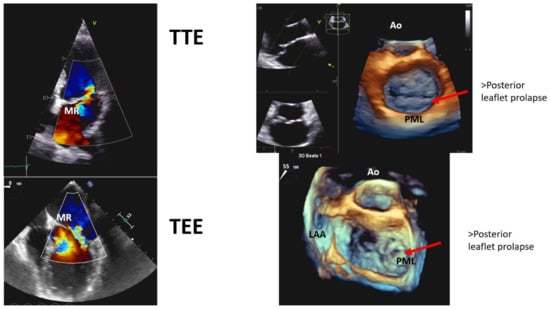

| TTE findings | Bileaflet prolapse |

| Myxomatous degeneration | |

| Moderate to severe MR (only in 36% of cases) | |

| Mitral annulus disjunction | |

| TEE | Additional information on MR severity |

| Detailed mitral valve anatomy | |